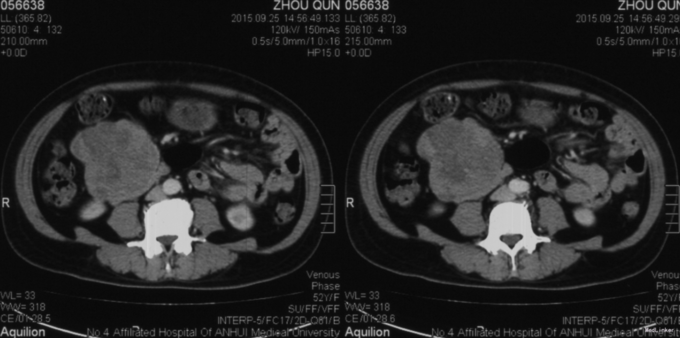

主诉:发现腹腔肿物1月余。 患者中年女性,在当地B超现实右侧中上腹软组织占位,行腹部增强CT显示右上腹腹膜后占位,考虑1、胰头实性假乳头状肿瘤,2、间质瘤,3、纤维肉瘤不能排除;脾大,右肾囊肿。当地B超引导穿刺活检:胰腺肿瘤,实性假乳头状肿瘤可能性大。为进一步手术治疗,来我院就诊。发病以来,患者无恶心呕吐、寒战高热,无腰背部放射痛,无皮肤巩膜黄染,食欲尚可,体力较好,体重无明显变化,二便正常。既往高血压病史16年,口服硝苯地、依那普利控制。

查体:腹稍隆,未见胃肠形,肠鸣音正常,约4次/分,未见腹壁静脉曲张,叩诊鼓音,肝脾肋下未及,脐右上可触及大小约10*10质韧肿块,边界清晰,无触痛,活动度稍差,墨菲氏征阴性;肝肾区无叩击痛,腹部无压痛及反跳痛,移动性浊音阴性。 辅查:外院B超、腹部CT、穿刺病理结果见病史。入院查:RBC 3.52*10^12/L,Hb 94g/L,余三大常规、凝血、病毒免疫、血脂未见明显异常。入院后MRI示:1、十二指肠降段近胰头区软组织肿块,考虑胰头钩突来源,实性假乳头状肿瘤肯能性大。2、慢性胆囊炎。3、双肾多发囊肿。